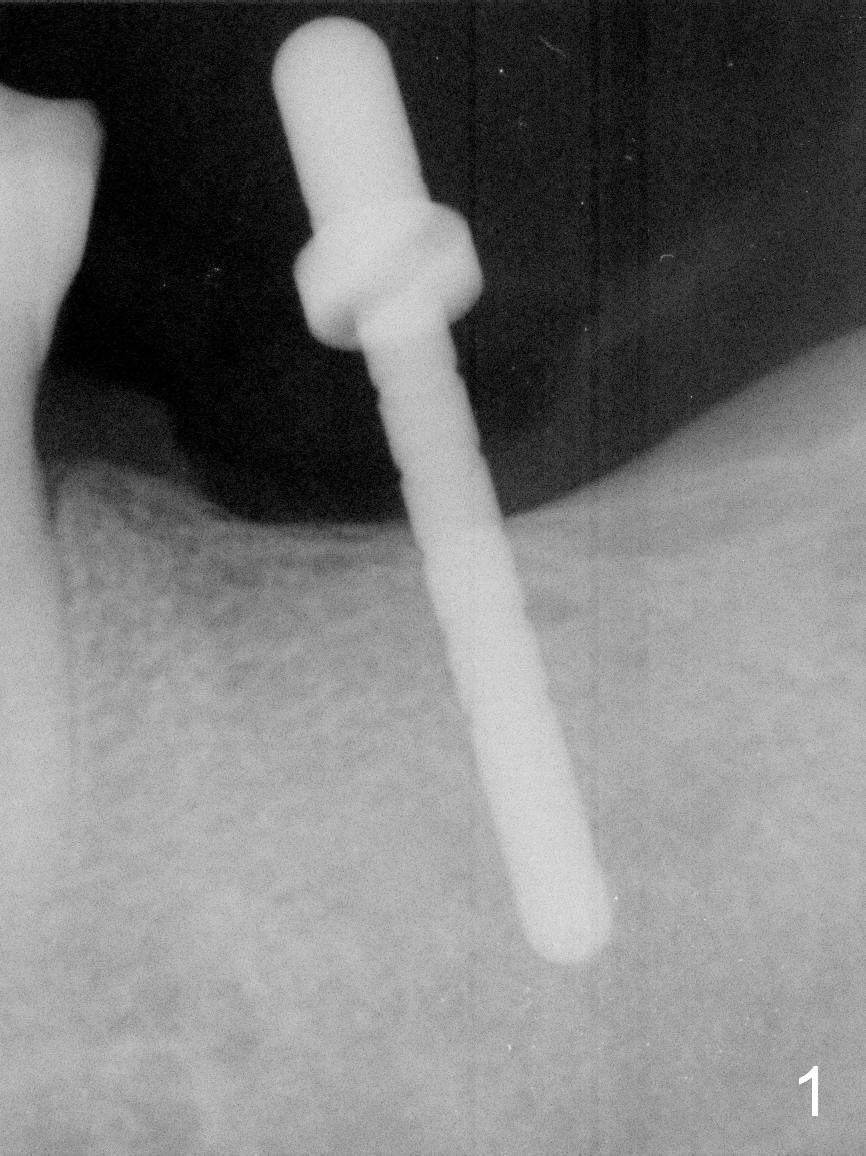

Implant Placed for Opposing Tooth Intrusion

A 4.5x8 mm Bicon implant is placed (Fig.1-3) with intent to intrude the supraerupted opposing tooth once a provisional is fabricated. Now it is 5 months postop. In spite of poor implant position, the abutment or the crown has not become loose with increased bone density around the implant 2 years 3 months post cementation (Fig.4: *). Guide could easily overcome the deficiency.